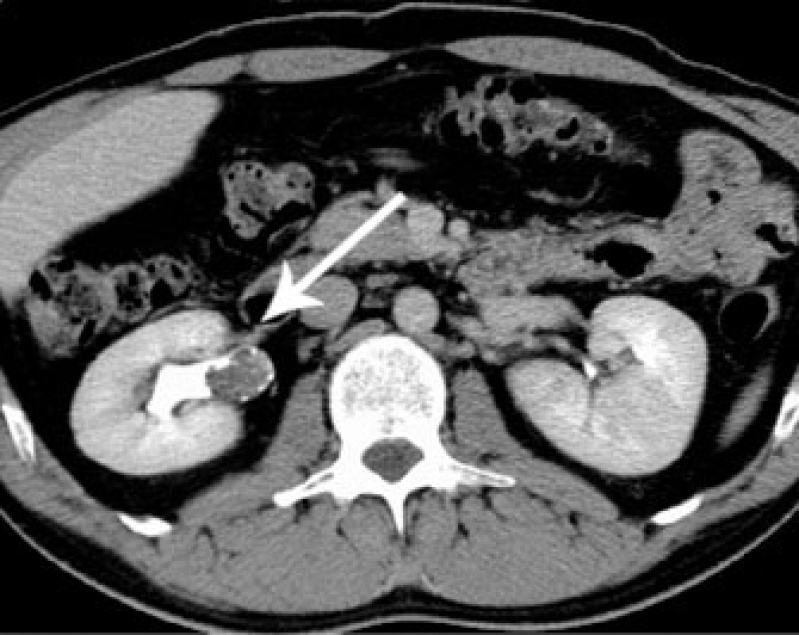

Exame de Imagem de Tomografia do Abdome Total

Medicom ExamesCom um exame de imagem é possível o médico analisar e ver o interior do corpo do paciente, para que desta maneira seja possível dar um diagnóstico para o paciente. O exame de imagem é diferente de...

Exame de Imagem de Tomografia do Abdome Total

Exame de Imagem de Tomografia do Abdome Total

Exame de Imagem de Tomografia do Abdome Total

Medicom ExamesCom um exame de imagem é possível o médico analisar e ver o interior do corpo do paciente, para que desta maneira seja possível dar um diagnóstico... Cotar Agora Saiba Mais